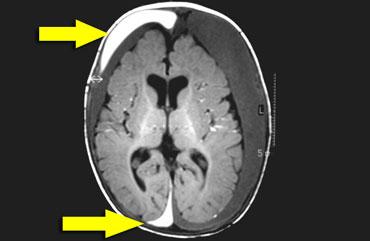

Các ổ dịch dưới màng cứng giảm âm hai bên giúp hiển thị rõ màng nhện (mũi tên). Tính chất đục của dịch gợi ý thành phần xuất huyết. Các khối máu tụ dưới màng cứng hầu như không có mạch máu, trái ngược với hệ thống mạch máu dưới nhện phong phú.

Máu tụ dưới màng cứng

Mặc dù xuất huyết có thể xảy ra ở bất kỳ vị trí nào, máu có xu hướng lan vào khe liên bán cầu (mũi tên trên hình bên phải).